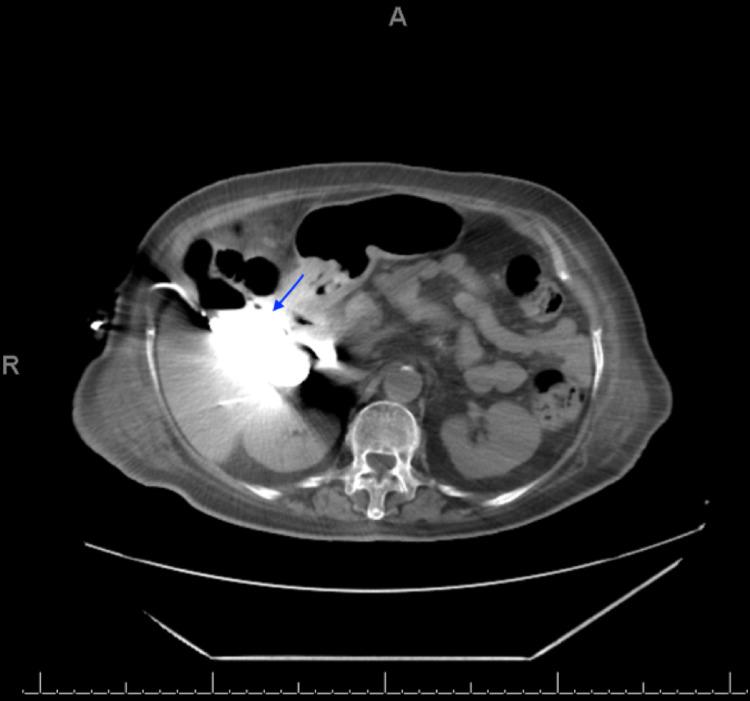

Gangrenous cholecystitis (GC), a severe complication of acute cholecystitis, is associated with higher morbidity and mortality rates than uncomplicated cholecystitis. In this report, we present the case of an 81-year-old female with diabetes mellitus and hypertension who presented in the emergency department complaining of severe generalized abdominal pain for 10 days. The pain was associated with nausea and vomiting. She had septic shock, prompting admission, and was eventually diagnosed with perforated GC. Interventional radiology was conducted, and a cholecystostomy tube was placed under radiology guidance with continuous daily irrigation and intravenous antibiotic coverage for four weeks. Subsequently, the patient's condition improved, and she was finally discharged.

坏疽性胆囊炎(GC)是急性胆囊炎的一种严重并发症,与非复杂性胆囊炎相比,其发病率和死亡率更高。在本报告中,我们介绍了一名81岁患有糖尿病和高血压的女性病例,她因严重的全腹痛10天而到急诊科就诊。疼痛伴有恶心和呕吐。她出现感染性休克,因此入院,最终被诊断为GC穿孔。进行了介入放射学检查,并在放射学引导下放置了胆囊造瘘管,每天持续冲洗,并静脉使用抗生素治疗四周。随后,患者病情好转,最终出院。